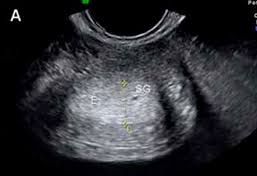

Debes saber que ambos ovarios contribuyen al crecimiento de los folículos. A partir de la semana 2 del embarazo se desarrolla lo que llamamos embrión que tiene básicamente una cabeza un tronco y una cola rizadaLas primeras semanas de embarazo son muy importantes porque aunque todavía es un embrión empieza a desarrollar los cimientos. Un embrión de 2 semanas es un ser humano. Se empieza a formar el embrión que mide 02 milímetros. Podemos ver dos sacos gestacionales en ambas imágenes con las siglas SG de 1 y 7 milímetros 41 y 44 semanas. Son las primeras estructuras del embarazo que se identifican por ecografía. Por ejemplo el embarazo aumenta el flujo de sangre a los senos por lo que es posible que sientas una sensación de hormigueo en los mismos o tengas los pezones muy sensibles. Esta semana de embarazo está marcada por. Semanas 1 y 2.